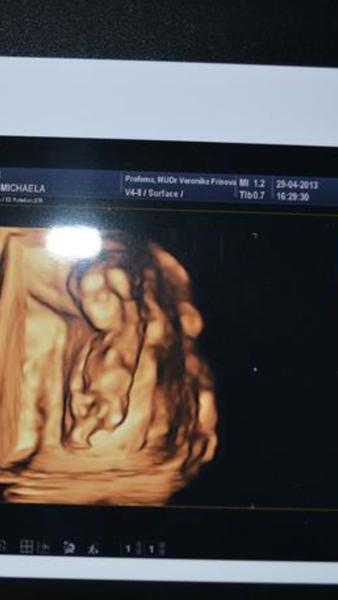

Já tam moc nevidím popravdě 🙂 pro srovnání přidávám fotku syna tehdy ve 13. týdnu - třeba to pomůže 🙂